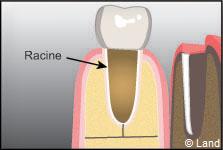

La dent est composée d’une couronne et d’une ou plusieurs racines incluses dans l’os alvéolaire.

La dent est articulée avec l’os alvéolaire par le ligament alvéolo-dentaire. Il agit comme un amortisseur entre la dent et l’os. Le cément est une couche mince recouvrant la racine et/ou les ligaments parodontaux rattachant la racine à l’os.